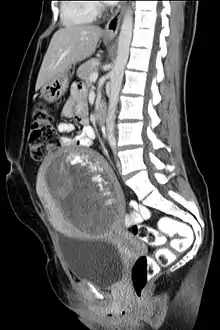

In rare cases a hydatidiform mole co-exists in the uterus with a normal, viable fetus. These cases are due to twinning. The uterus contains the products of two conceptions: one with an abnormal placenta and no viable fetus (the mole), and one with a normal placenta and a viable fetus. Under careful surveillance it is often possible for the woman to give birth to the normal child and to be cured of the mole.[9]